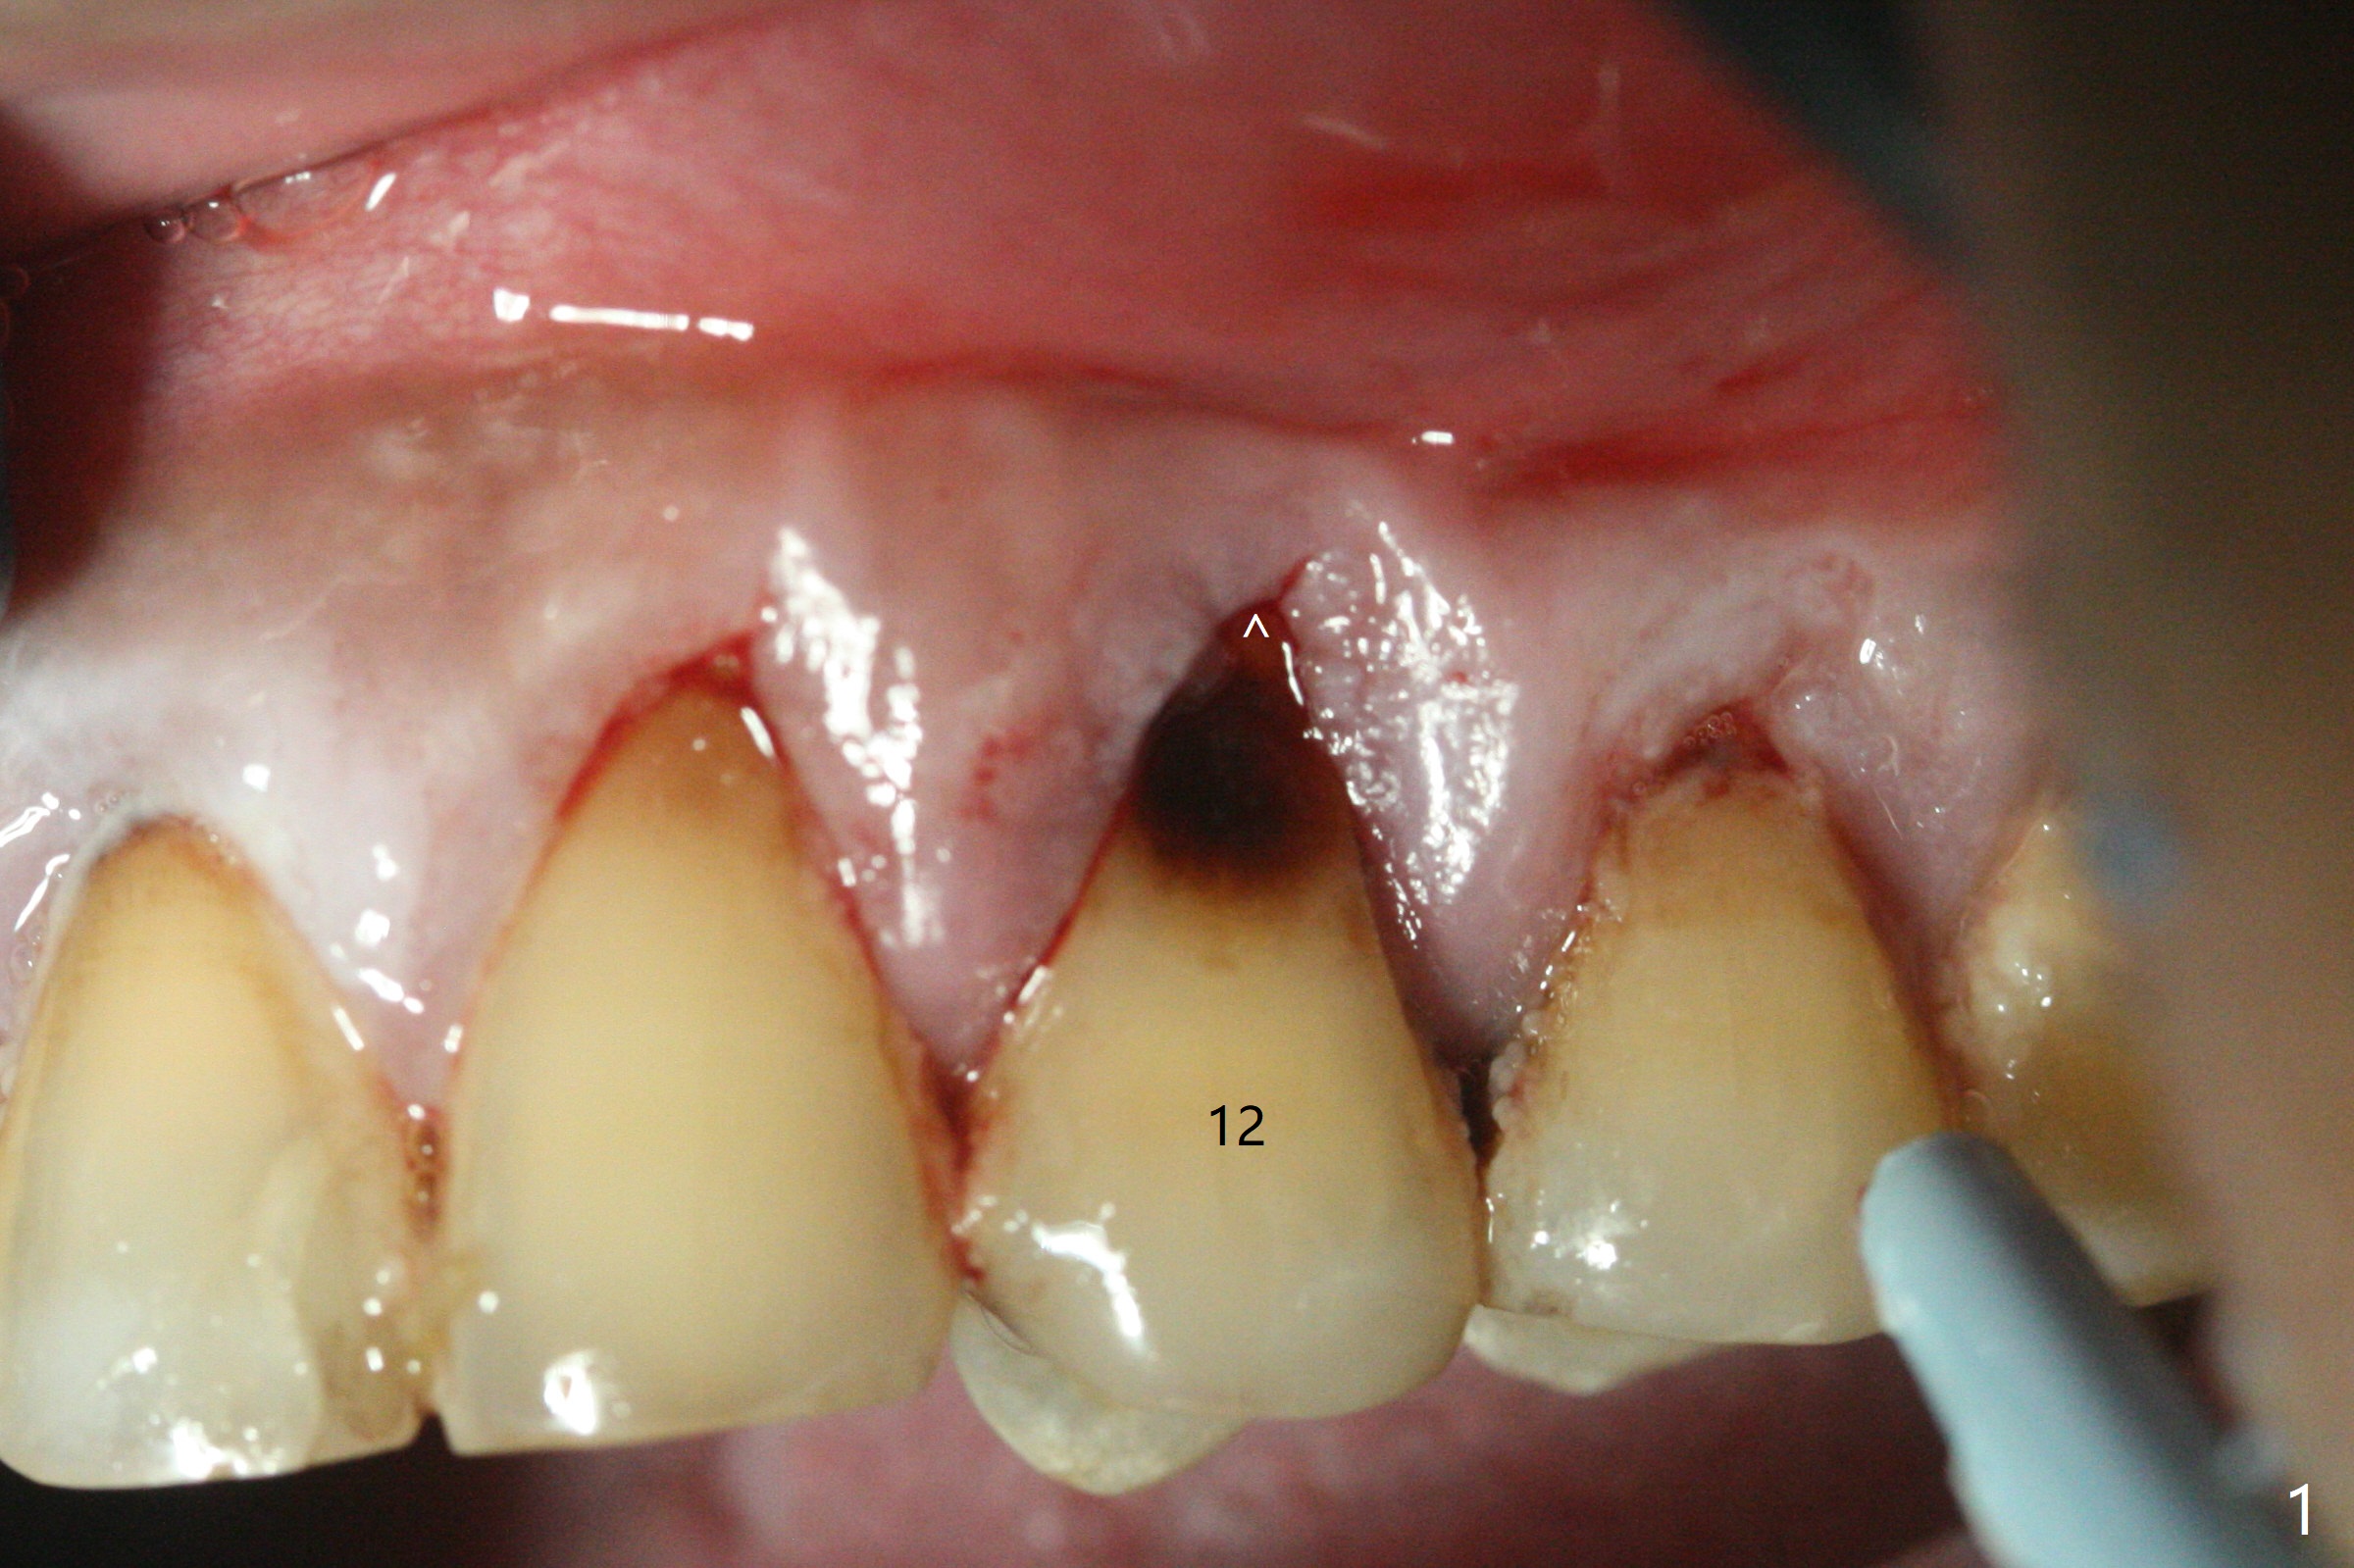

拔牙前发现患牙颊侧牙龈退缩(图一),需要软组织移植吗?拔牙后,在根尖用1,1.5,2.0 和3.0毫米骨凿打穿窦底,然后输入粘性骨粉(图四:*)。腭侧骨壁建立钻洞(有利于颊侧牙龈再生),忘了拍摄先锋钻根尖片,直接植入4x14毫米软组织水平报废植体,接近尖牙牙根(图二(黄虚线:窦底))。木已成舟,无法改变方向,又没有更长植体,只好植入同样大小植体(图三),即刻放置基台,固定骨粉和PRF膜,后者促进颊侧退缩牙龈再生,最后使用树脂敷料封闭伤口。